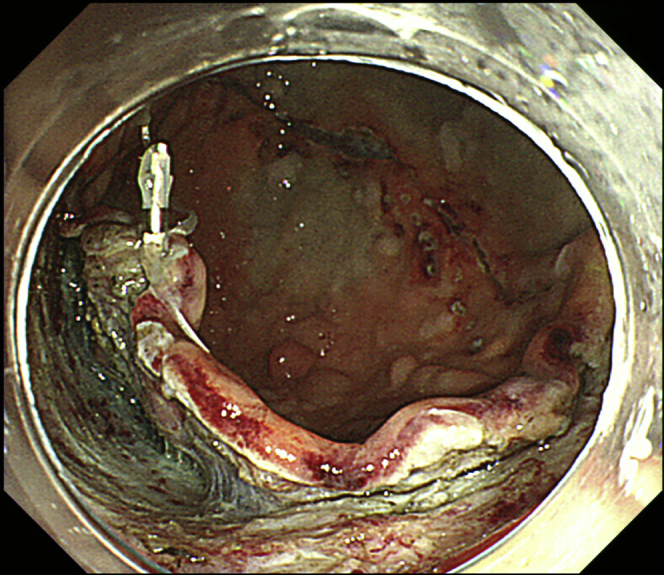

Figure 6.

Patient’s position and multiple clip-line traction allow satisfactory tissue traction to be maintained until the end of the procedure.